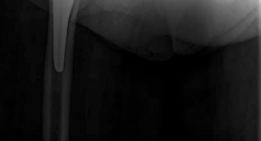

Offset broach handles are essential to clear the soft tissues of the lateral thigh. The femur is broached sequentially. Fluoroscopy is used to confirm the size, alignment, and depth of the broach. A trial neck and head are placed.

Reduction and Closure

The hip is reduced by applying axial traction and internally rotating the limb. Fluoroscopy is used to assess leg length (comparing the teardrop-to-lesser trochanter distance bilaterally) and offset. Clinical stability is tested by taking the hip through a full range of motion, specifically checking for anterior impingement in extension and external rotation.